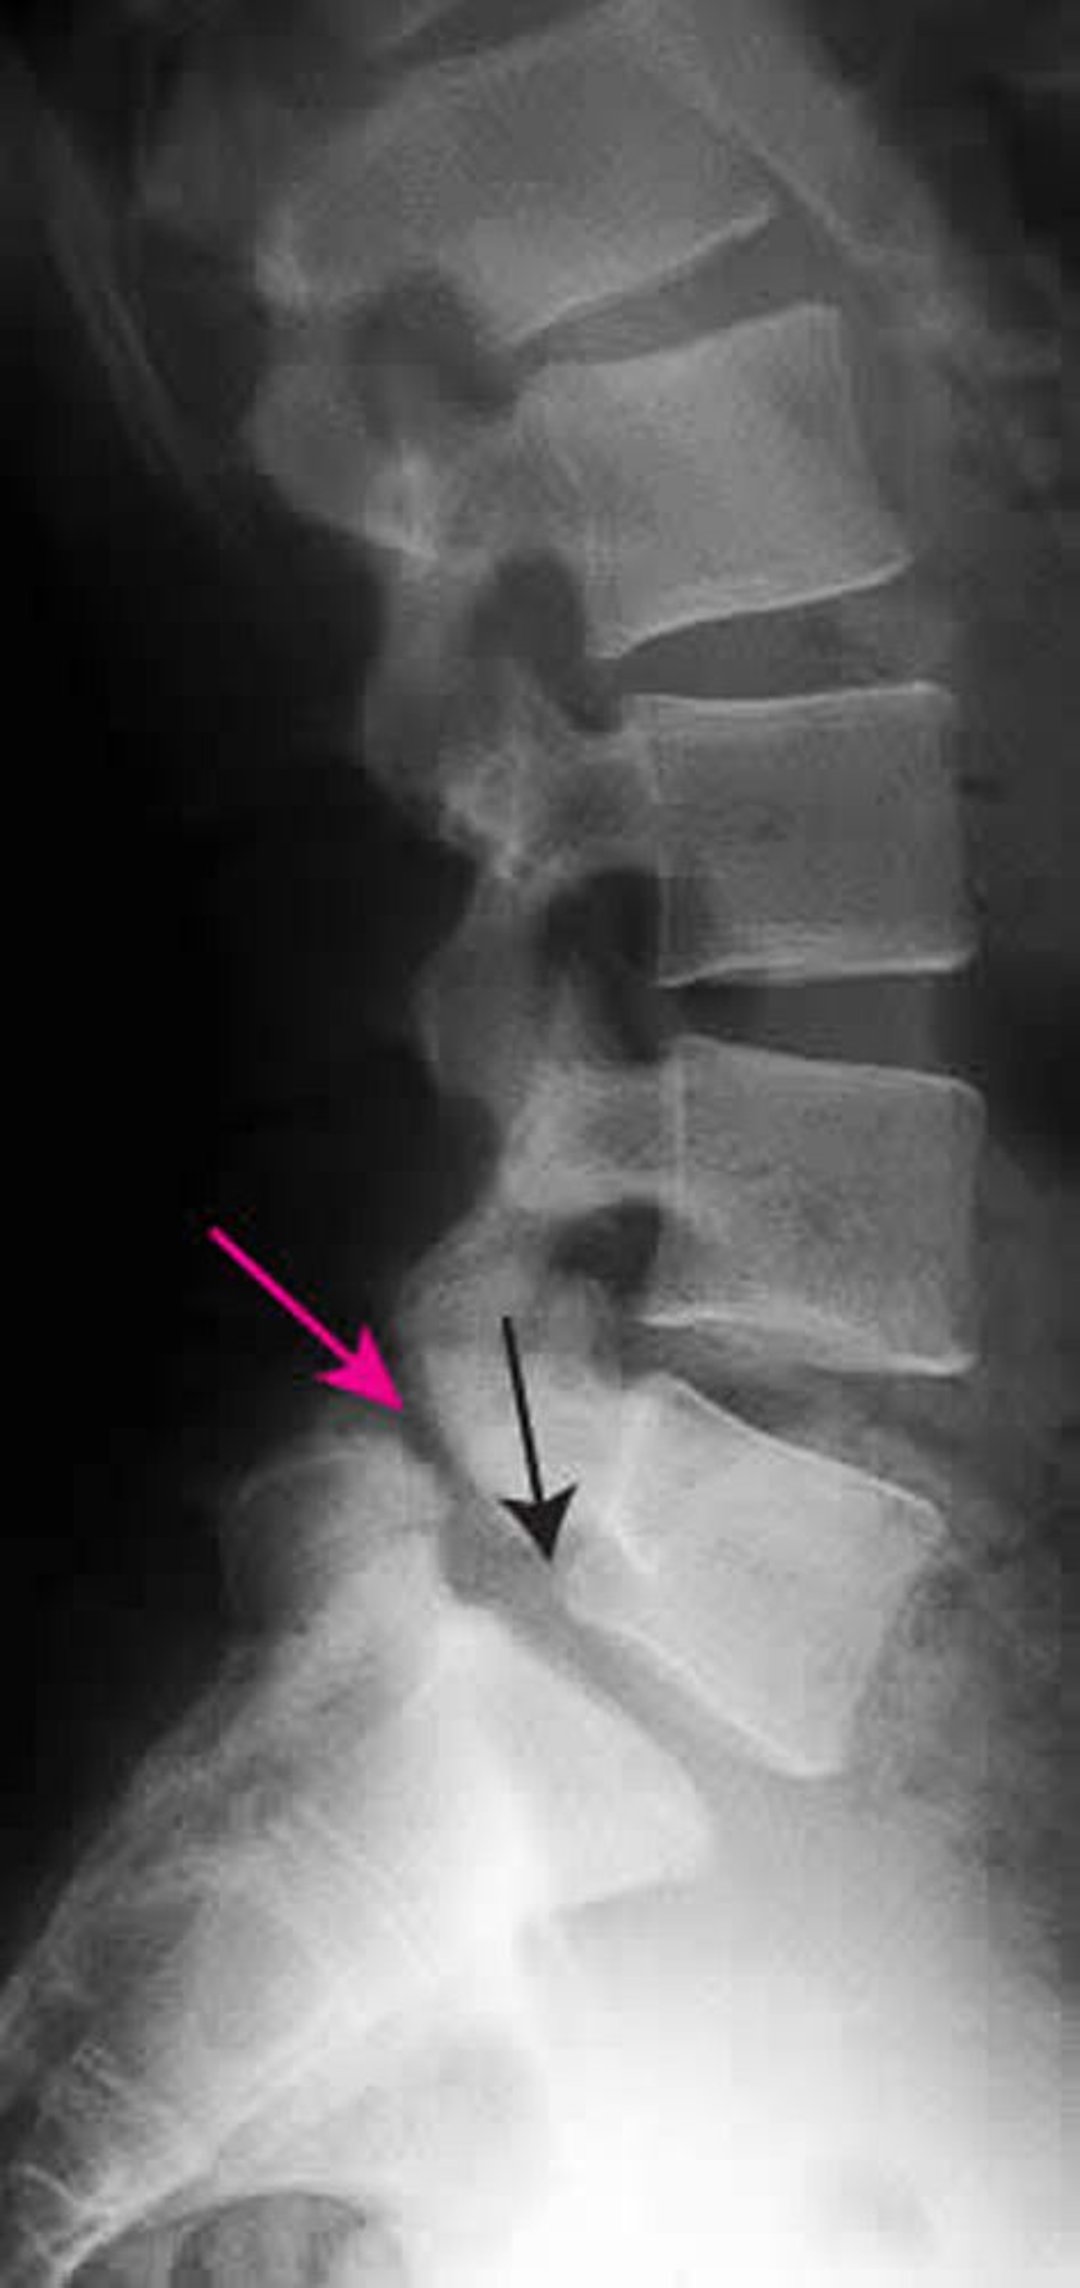

Espondilolistesis

Esta radiografía muestra espondilolistesis de grado 1 de L5 sobre S1. La flecha negra muestra el borde posterior de L5, que subluxa por delante de S1. La flecha roja señala la espondilólisis (defecto en la parte interarticular).

ZEPHYR/SCIENCE PHOTO LIBRARY